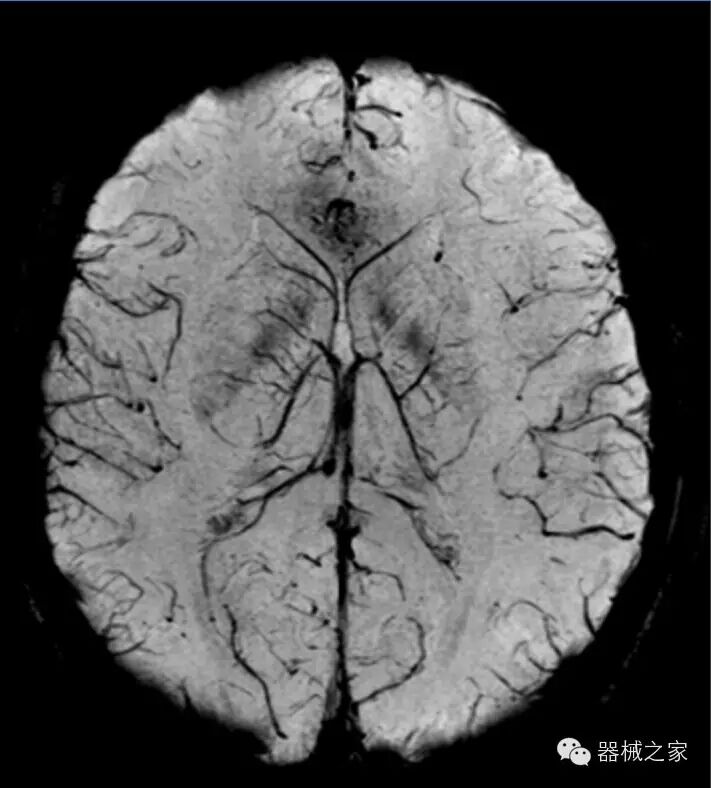

头部SWI

·SWI和SWIM,即磁敏感加权成像和定量分析;